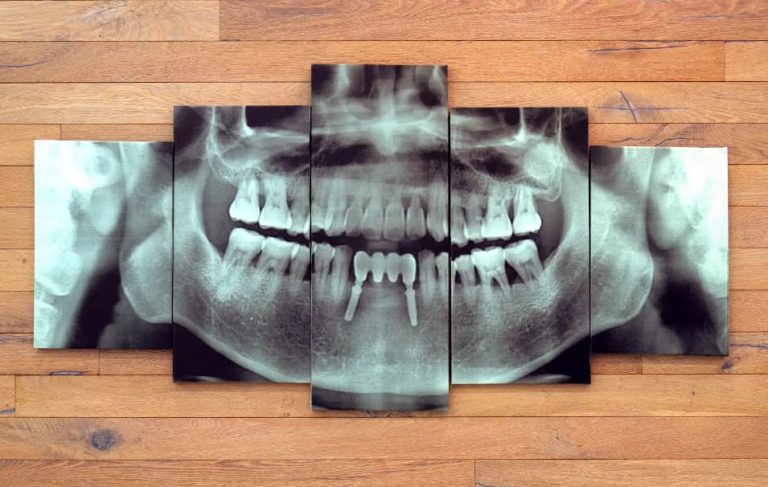

Dental implants are small titanium posts that are carefully placed into the jawbone to serve as replacements for the roots of missing teeth. These implants provide a secure and durable foundation for artificial teeth such as crowns, bridges, or dentures. At Smile Point Dental, we utilize advanced methods and personalized care to ensure your dental implants are functional, long-lasting, and look completely natural.

Dental implants are one of the most natural-looking and practical solutions for replacing missing teeth. They are a leading treatment in modern dentistry requiring highly skilled specialists’ expertise. At Smile Point Dental in Oakville, we proudly offer exceptional dental implant services tailored to your needs while keeping costs affordable.